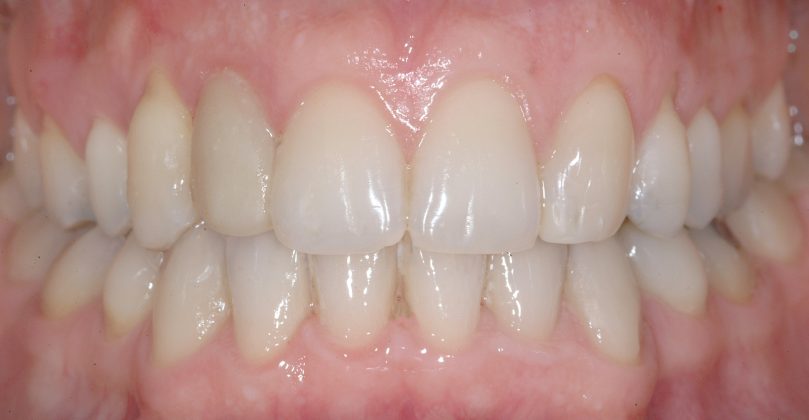

Al termine del trattamento ortodontico, che ha richiesto 24 mesi di terapia, è stata applicata una contenzione fissa3 all’arcata inferiore mediante filo multi-intrecciato coassiale .0195” esteso da 4.4 a 3.5 al fine non solo di stabilizzare il risultato sia sul piano orizzontale sia verticale, ma soprattutto per prevenire adeguatamente l’affollamento dentale terziario (Figure 9a-e).

All’arcata superiore è stato mantenuto il pontic in composito in sede 1.2, poiché la paziente, per esigenze personali, aveva preferito rimandare a un tempo successivo la sostituzione implantare di 1.2 agenesico, così come la coronoplastica definitiva di 2.3.

Dopo tre anni dal termine del trattamento ortodontico, la paziente ha richiesto di finalizzare il suo caso; è dunque stata effettuata la sostituzione implanto-protesica dell’elemento 1.2, senza necessità di ulteriori rifiniture ortodontiche, avendo mantenuto, grazie al pontic in composito, un ottimo parallelismo radicolare tra 1.1 e 1.3.

È stata eseguita contestuale terapia rigenerativa, per ottimizzare qualità e quantità dei tessuti nel sito implantare. Come si rileva dalle immagini di follow up, dopo la fase implanto-protesica superiore, è stata applicata anche una parziale contenzione fissa tra gli incisivi centrali superiori e il risultato ortodontico si è mantenuto stabile nel tempo (Figure 10 a-e).